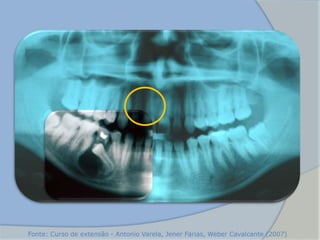

 Necrose pulpar

 Apresentam-se como radio transparência arredondada circunda o

ápice do dente

 Observa-se perda da lâmina dura ao longo da raiz adjacente

 A reabsorção é comum

• Características

Radiográficas

(NEVILLE, 2004)